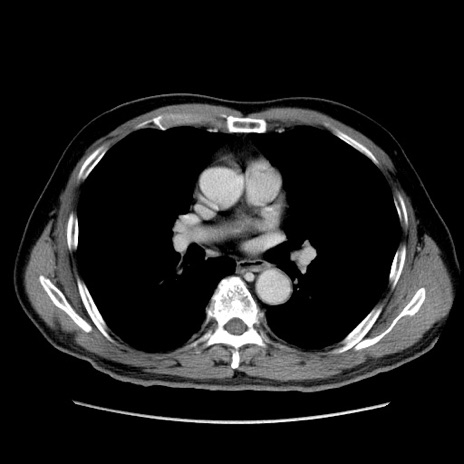

症例34(横断像)

【症例】60歳代 男性

【主訴】右鼠径部膨隆

【現病歴】1年程前より右鼠径部膨隆あり。自己にて還納可能だったため放置していた。3時間前より右鼠径部の脱出を認め、還納困難となり受診。

【既往歴】高血圧

【身体所見】右鼠径部に小児頭大の膨隆あり。弾性硬であり、用手還納は困難。左鼠径部にも膨隆を認める。脱出はなし。

【データ】WBC 15500、CRP 測定なし